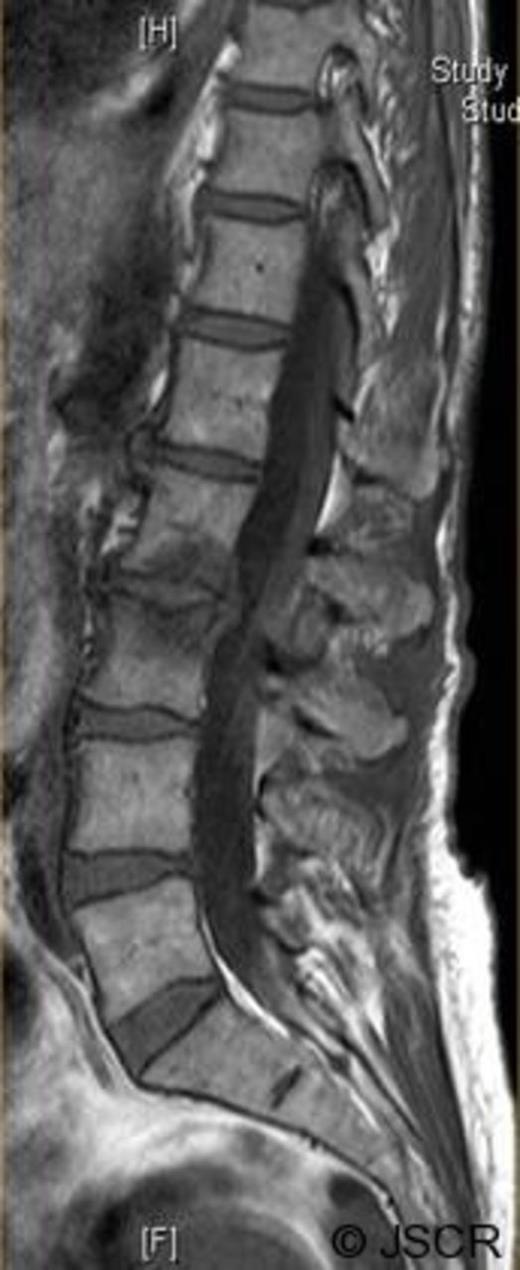

Magnetic Resonance Imaging scan (Fig. 1–4) showed L2/3 disc prolapse impinging on the right exit canal and causing L2 and L3 compression, thus she was listed for L2/3 lumbar discectomy and decompression. Examination of the right L2/L3 dermatomes revealed severe paresthesia and mild grade 4/5 weakness; reflexes were all normal. All other neurological examination was normal.

Preoperative sagittal T1 weighted image showing disc bulge at L2/3